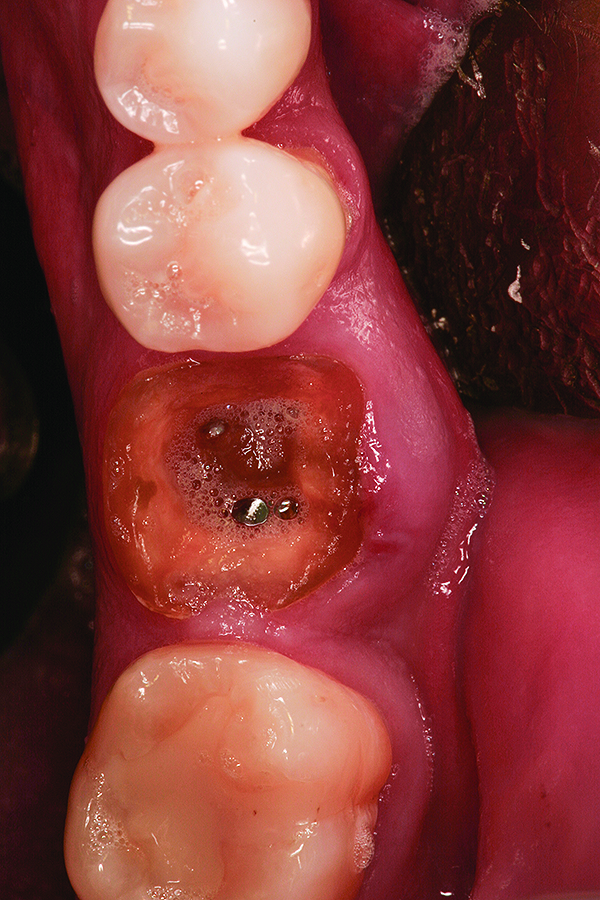

Fig 11. Intentional non-primary closure following the placement of an amnion-chorion barrier over the bone allograft.

Figure 11

Fig 12. Note the significant formation of bone and repair of the buccal osseous defect at 3 months healing.

Figure 12